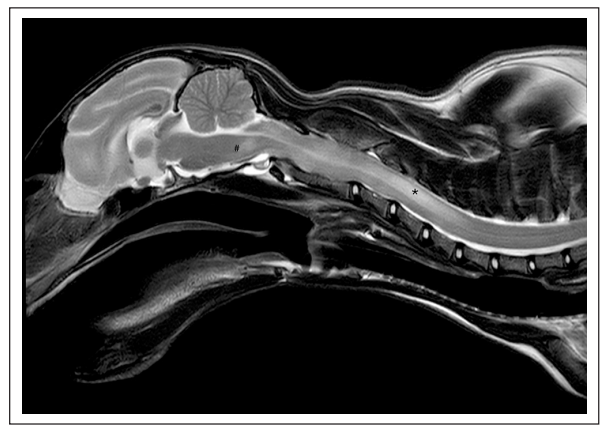

第66天,进行了高场强脑部和颈椎MRI检查。发现延髓至C5的髓内病变、脊髓肿胀(图1)、中度脑室扩大(图2)以及多灶性脑膜增厚且对比增强显著(图3)。肿胀限制了对枕大池的通路,因此需要进行腰椎穿刺而不是寰枕部穿刺以获取脑脊液。

↑ 图1. 大脑和颈椎的矢状位T2W图像。可见中度脊髓肿胀,以及中脑处存在一个广泛的、不对称的T2W和T1加权高信号病变(#),该病变沿颈椎延伸至C5。该病变在C4水平(*)最为明显。